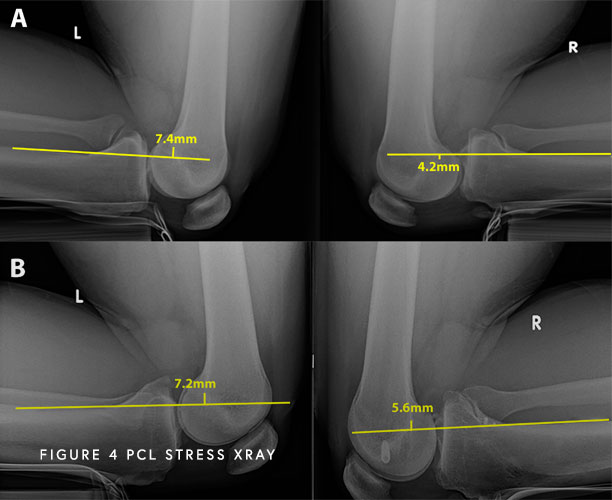

Objective Use Of Stress Radiographs